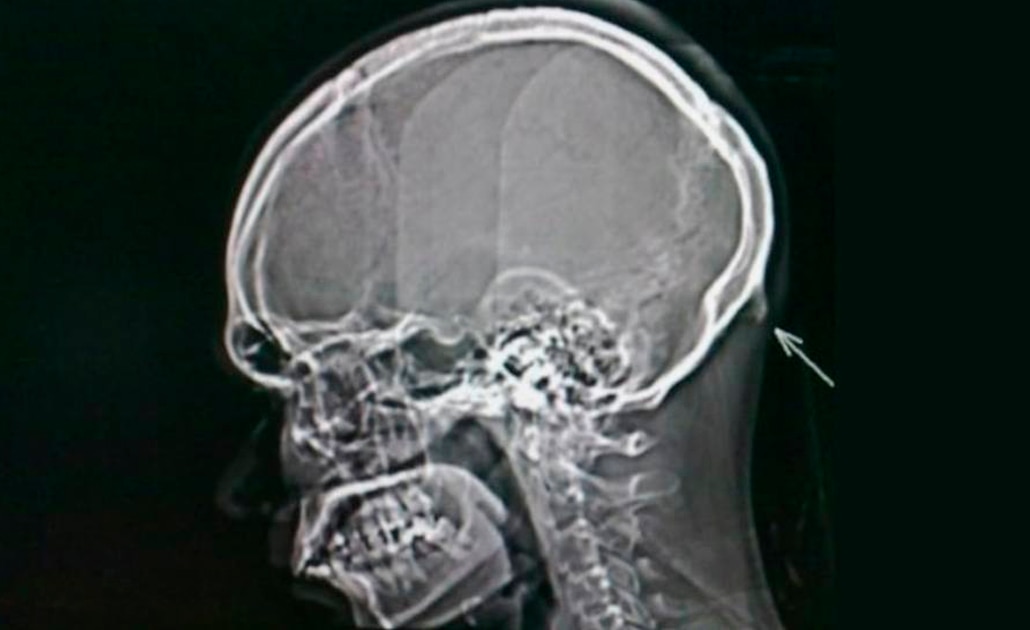

Un grupo de científicos de la Universidad de Sunshine Coast, en Australia, descubrió que el uso de smartphones está provocando el crecimiento de una especie de “cuerno” en el cráneo humano